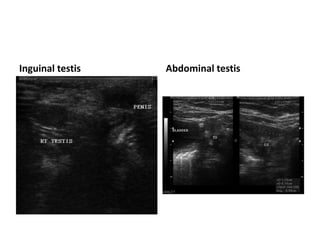

Imaging of UDT

 U/S-good for inguinal testes, not reliable if higher

Inguinal testis Abdominal testis